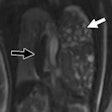

Case report: Conjoined twins -- thoraco-omphalopagus (type A)

December 9, 2015